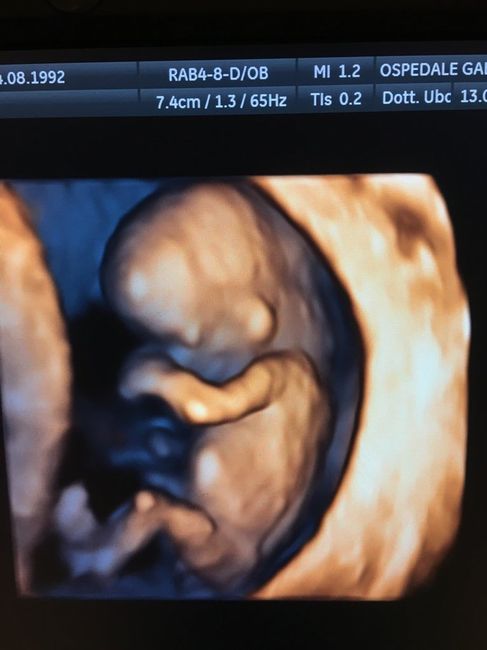

Secondo il ginecologo è una femminuccia

È stata per me L ecografie più emozionante di tutte, vederlo tutto formato e saltare da una parte all altra è qualcosa di indescrivibile, vi allego le fotine